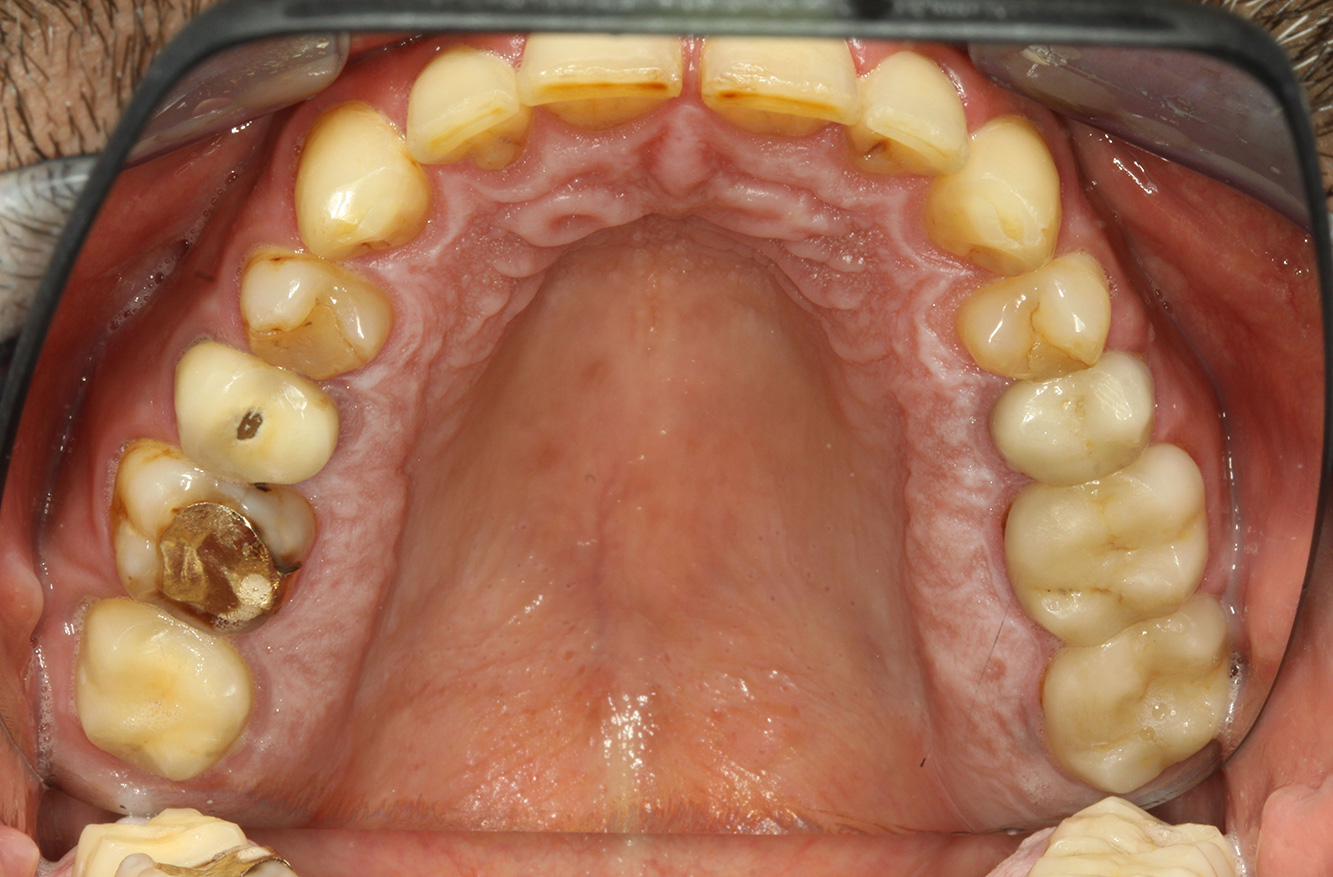

El paciente tiene 39 años con valvuloplastia frente a una insuficiencia valvular y endocarditis. Toma regularmente ASS 100 (ácido acetil salicílico) como anticoagulante. En el ámbito del estilo de vida, la alimentación se identifica como promotora de caries, ya que suele consumir alimentos azucarados y seis o siete comidas al día. La salud oral del paciente muestra un riesgo medio de caries con lesiones activas. El riesgo de periodontitis es bajo, presenta gingivitis. Se hacen las siguientes recomendaciones para el tratamiento profiláctico.

Para la sesión de profilaxis no hay recomendaciones específicas de instrumental. Mediante el uso dirigido de un aeropulidor y del pulido rotativo, puede eliminarse suavemente la placa y la decoloración en los bordes de la restauración y reducirse los nichos de recolonización para bacterias carcinógenas (19).

Para prevenir aún más las caries, se recomienda la fluoridación, especialmente para prevenir la nueva formación en el área de los márgenes de restauración y para sellar las superficies radiculares. Ambas medidas pueden reducir la sensibilidad a la temperatura de los dientes.